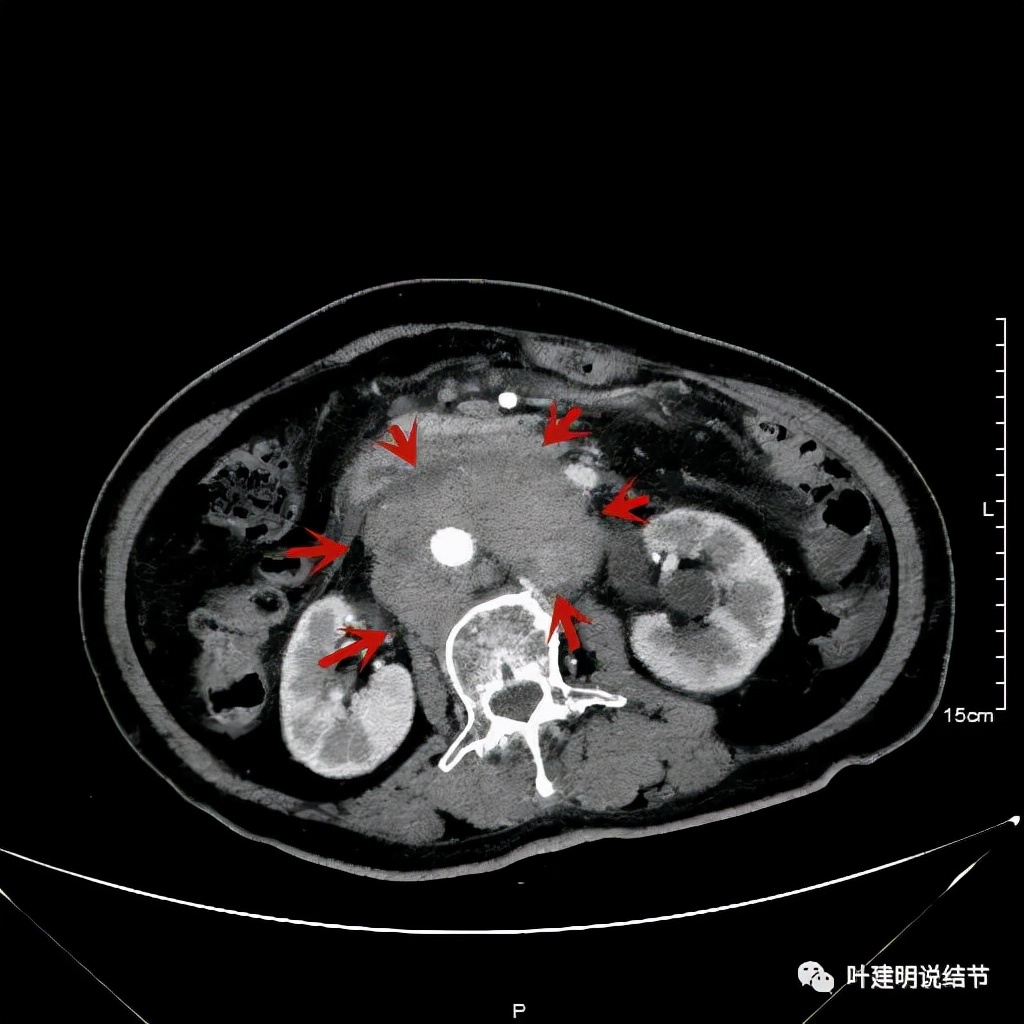

之后又再经过一个周期后的对比:

上图同样左侧是治疗前的,右侧经过2周期免疫加化疗后复查的,可见病灶缩小甚至超过9成。下面是治疗前与后来于6月底复查的: